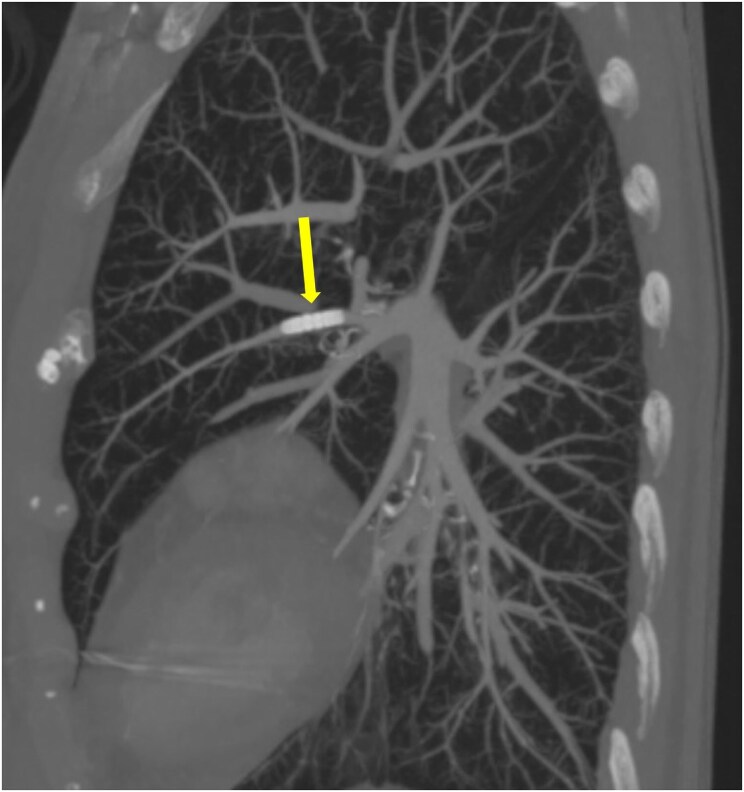

Case summary: An 82-year-old lady underwent PPM implantation for symptomatic 9-second sinus pause. During procedure, the anchoring sleeve from the atrial lead embolized through cephalic vein to the left superior lingular artery. The patient remained haemodynamically stable and multimodality imaging demonstrated only a small affected area of lung with patent pulmonary blood flow distal to the sleeve. Therefore, the patient was managed with anticoagulation alone and has remained well at 26-month follow-up.